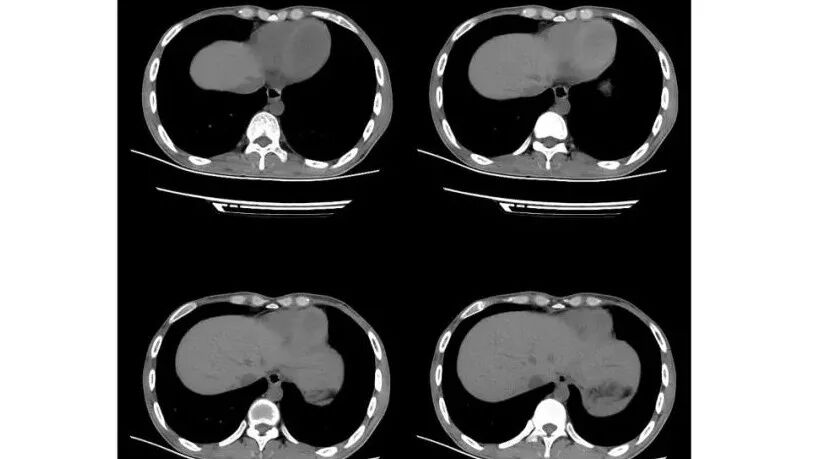

影像与临床:1.青年男性,HlV阳性,颜面部皮疹(未提供皮疹图像)、发热(高热),实验室CRP、PCT高,T-Spot阴性。2.右肺下叶空洞结节,壁厚不均,边界清楚,其内线状影,未见液平及钙化,未见卫星灶,纵隔淋巴结增大,双侧腋窝见增大淋巴结。心腔内低密度提示贫血可能。肝脾影增大,未见结节影及块影。腹膜后见多发增大淋巴结。

综合分析:本例肺部影像学改变并不具有特征性,空洞性病灶须与多种疾病鉴别,但年轻HIV阳性患者,高热,皮疹,肝脾增大,纵隔、腋窝、腹膜后见多发增大淋巴结等都强烈提示马尔尼菲篮状菌感染的可能性。